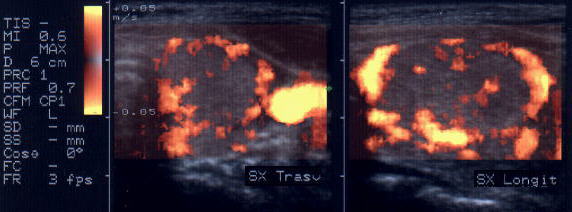

Femeie 25 ani. Nodul unic in lobul stang, contur net, hipoecogen, respecta parenchimul din jur, neomogen, de 18x23x36 mm (7,5 cc).

Citoaspiratia cu ac subtire: nodul adenomatos.

Examen histologic postoperator: adenom trabecular fetal.

Acelasi caz. La doppler color - vascularizatie interna, mai evidenta in powerdoppler.